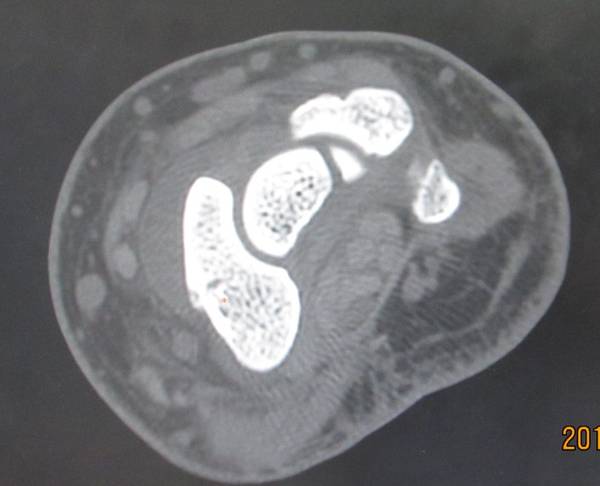

今天去ct室拍了一组舟骨骨图片

在机房看的动态的图像,想怎么看就怎么看

随便转

对骨质结构情况一目了然

太清楚了

4.png

2.png

1.png

3.png